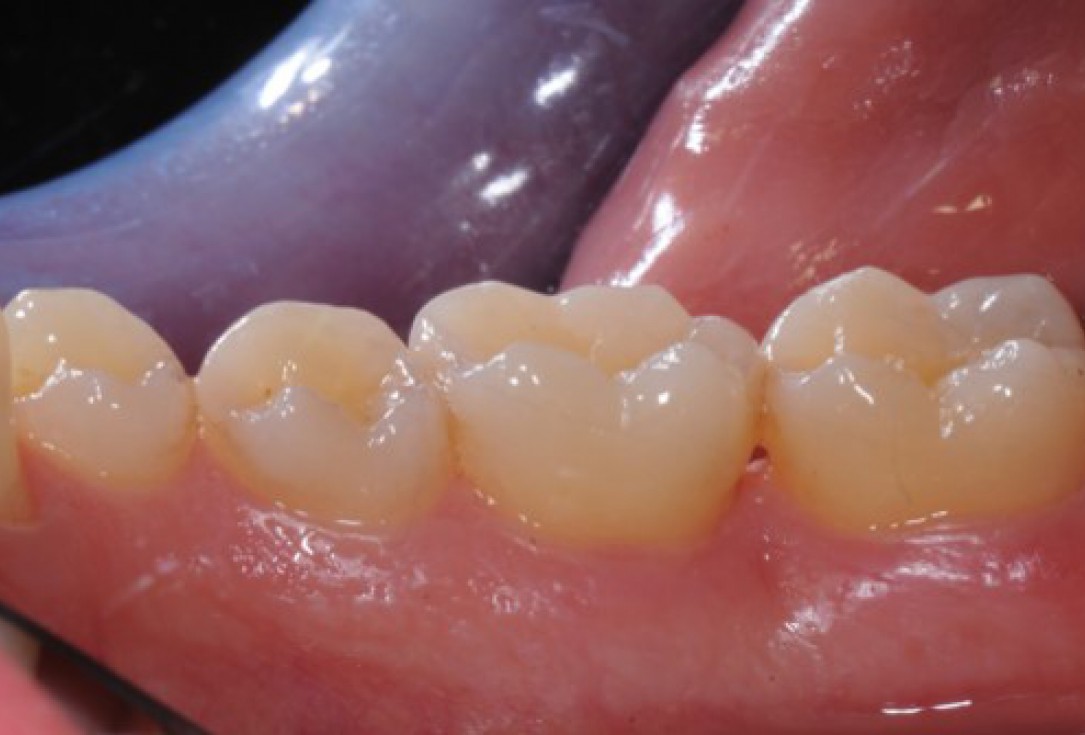

Pre-operative clinical situation. Shallow multiple adjacent gingival recessions in the first quadrant.